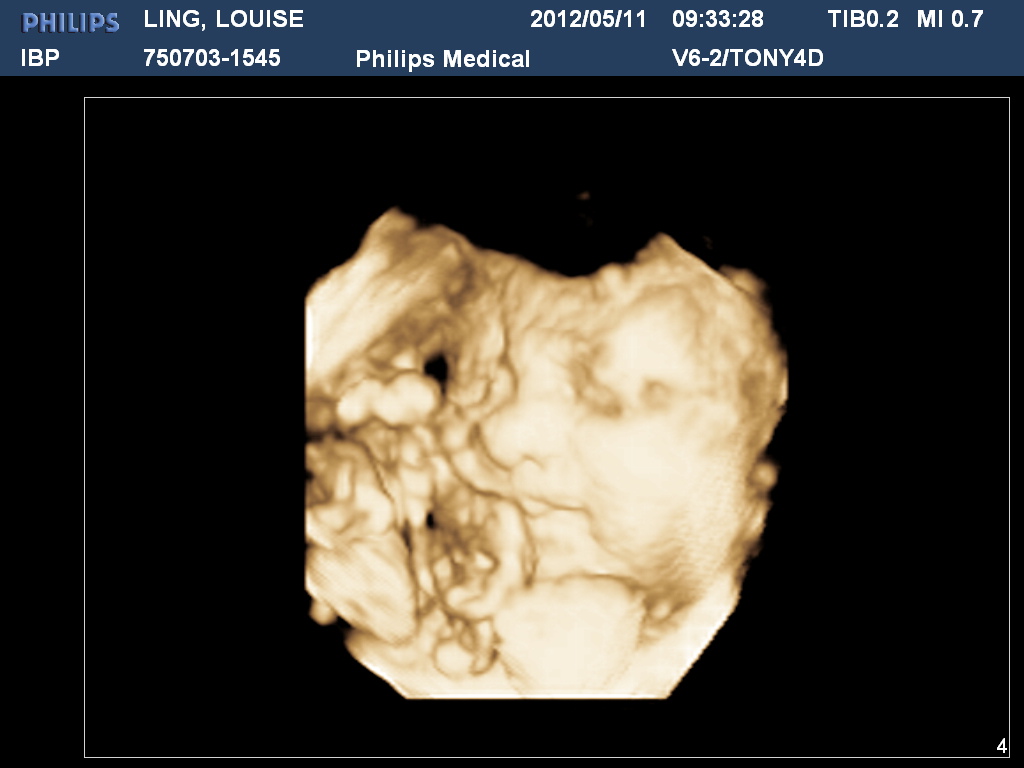

These days, you end up knowing so much about your baby before it’s even been born. By the time Bubba made her long-awaited arrival, we’d had 7 ultrasounds! This was mainly due to us being special needs in the fertility department and then whack on some concern about Braxton Hicks and going over our date and voila, we’d had a peak 7 times and knew everything about her, apart from her gender. For us it certainly made the delivery much more exciting, and when I say exciting I mean it was a nice reward after fuck loads of pain.